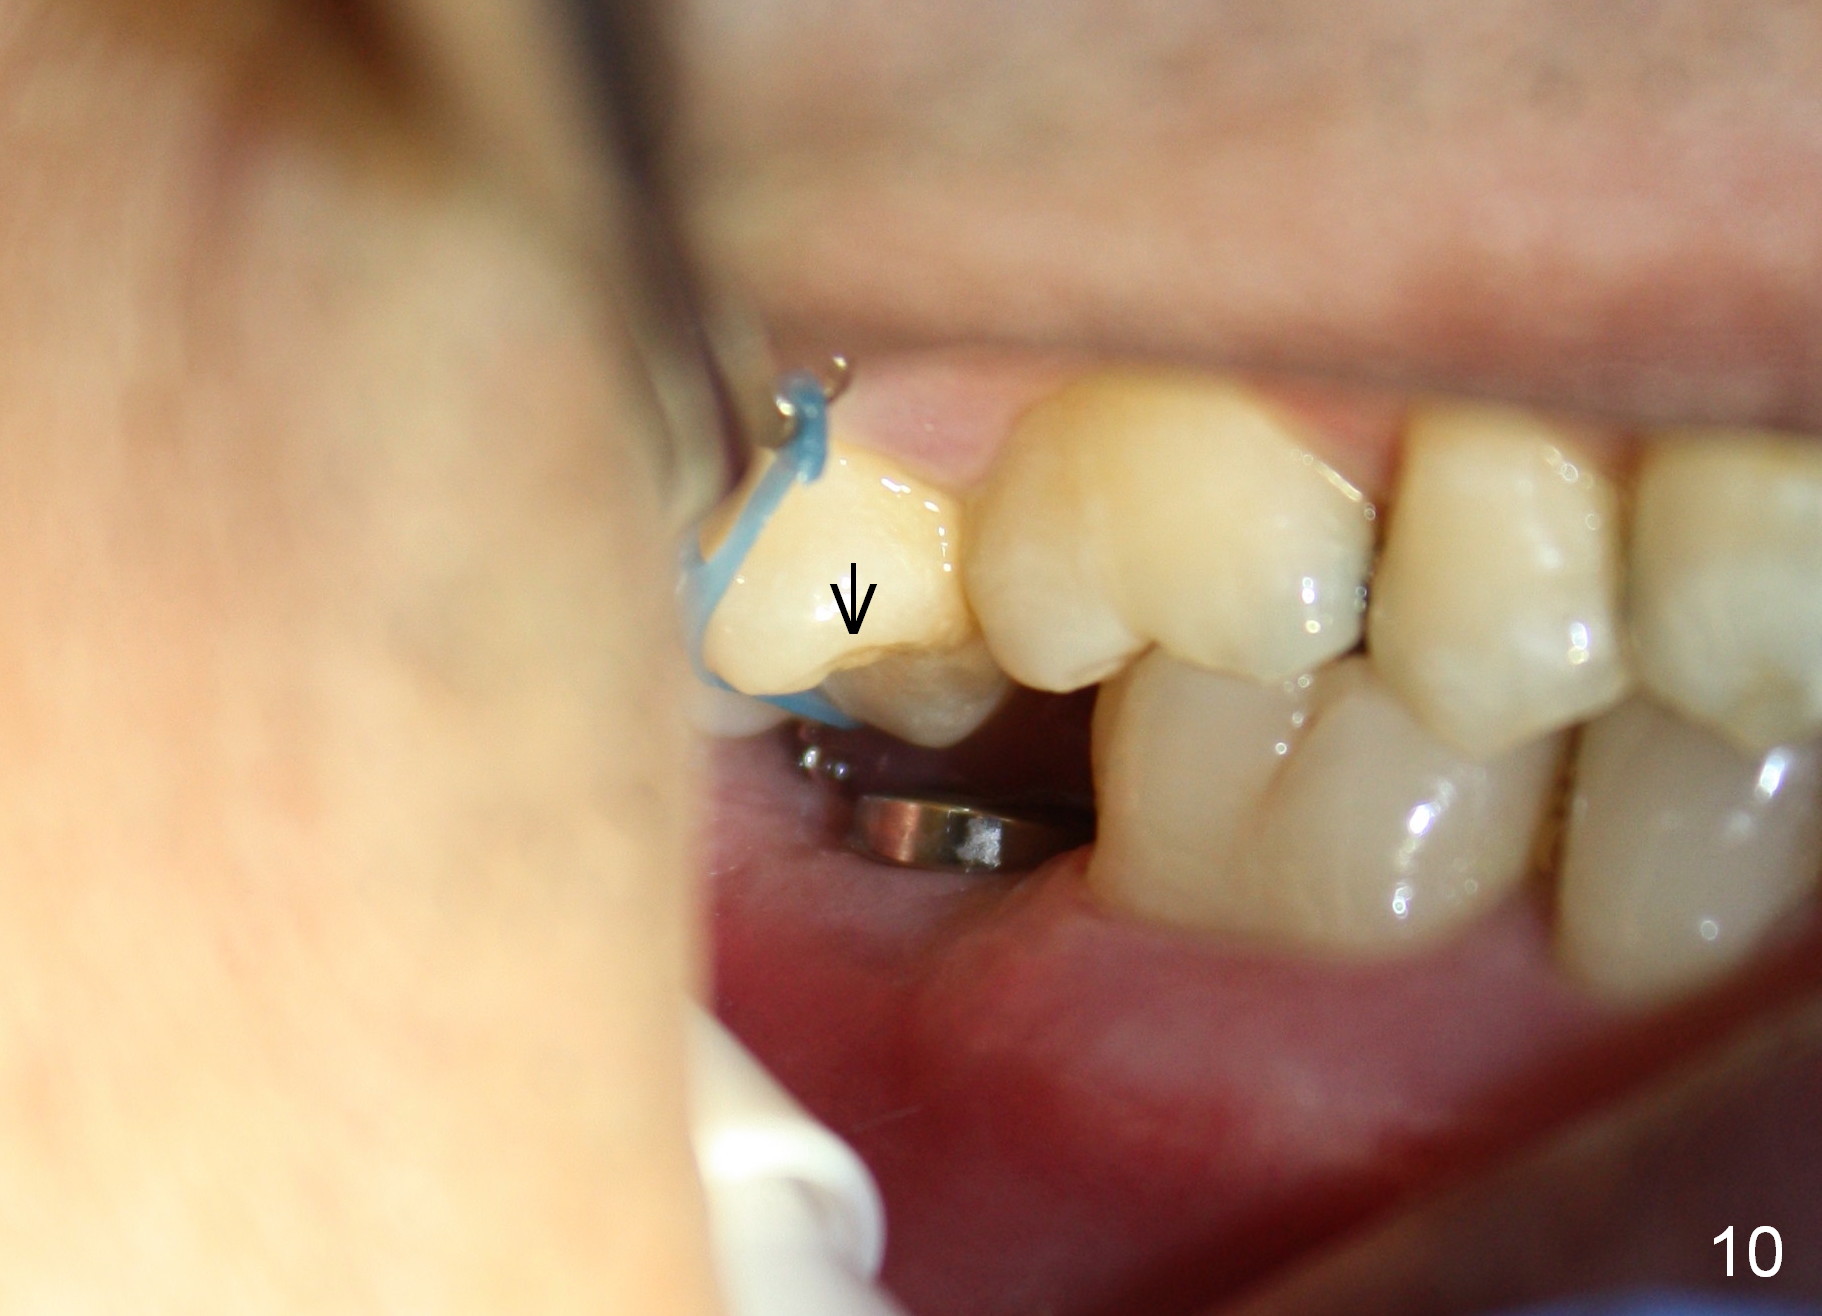

The wound heals uneventfully (Fig.8,9: taken 3 months postop). When an abutment is placed, there is no clearance for a crown. Two mini-implants are placed for the tooth #2 intrusion (Fig.10,11). Four months later, segmental orthodontic appliance is added because of lack of result of intrusion and buccoversion of the tooth #2 (Fig.12). Two months later, all of orthodontic treatment is terminated at the request of the patient. After heavy reduction of the tooth #2, a crown is cemented. Fig.13 (panoramic X-ray) is taken 11 months post cementation. There is no bone loss nearly 3 years post cementation (Fig.14).